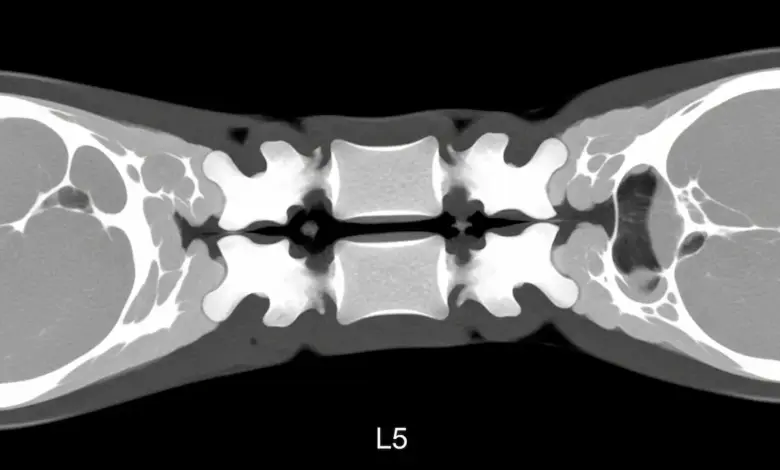

Ocorre com maior frequência em L5 e L4, costuma surgir por microtraumas repetidos e pode aparecer sem sintomas.

- A tomografia confirma a linha de fratura.